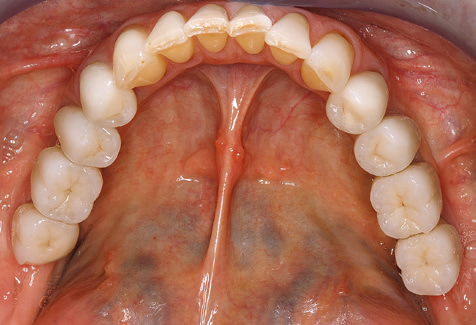

Un paziente di 52 anni si è presentato nella nostra clinica per la prima volta nel 2004 a seguito della perdita dei denti nel terzo quadrante, esprimendo il desiderio di un nuovo restauro protesico. La diagnostica parodontale e radiologica ha rivelato la necessità di un ampio trattamento parodontologico. Inoltre, ai denti 48, 28 e 27 è stata attribuita una prognosi molto scarsa e sono stati successivamente estratti (Fig. 1). A seguito del trattamento periodontologico sistematico completato con successo, è stato inserito una protesi dentale fissa con l'inserimento di cinque impianti nelle regioni dentali 35, 36, 37, 46 e 47. Il trattamento protesico dei denti naturali è stato effettuato con corone rivestite in ceramica di biossido di zirconio; gli impianti two-piece composti da abutment singoli in biossido di zirconio e corone similmente rivestite in ceramica di biossido di zirconio (base Cercon colorata, Dentsply Sirona Lab). L'inserimento definitivo del restauro protesico è avvenuto nel 2005.

A causa della presenza di problematica parodontale, SPT è stata eseguita ogni tre mesi nei primi anni successivi all'inserimento. Il paziente ha dimostrato un alto grado di motivazione e una buona costanza. Le profondità di tasca registrate ogni anno hanno rivelato una situazione parodontale stabile con un indice BOP inferiore al cinque per cento. Sulla base della situazione parodontale stabile e della buona collaborazione da parte del paziente, l'intervallo di richiamo è stato esteso ogni sei mesi a partire dal sesto anno dalla fase della funzione protesica. A seguito della modifica dell'intervallo di richiamo, la rispettiva documentazione annuale dello stato parodontale ha continuato a rivelare una situazione parodontale stabile senza aumento della profondità della tasca e un indice BOP inferiore al cinque per cento (Fig. 2a eb).